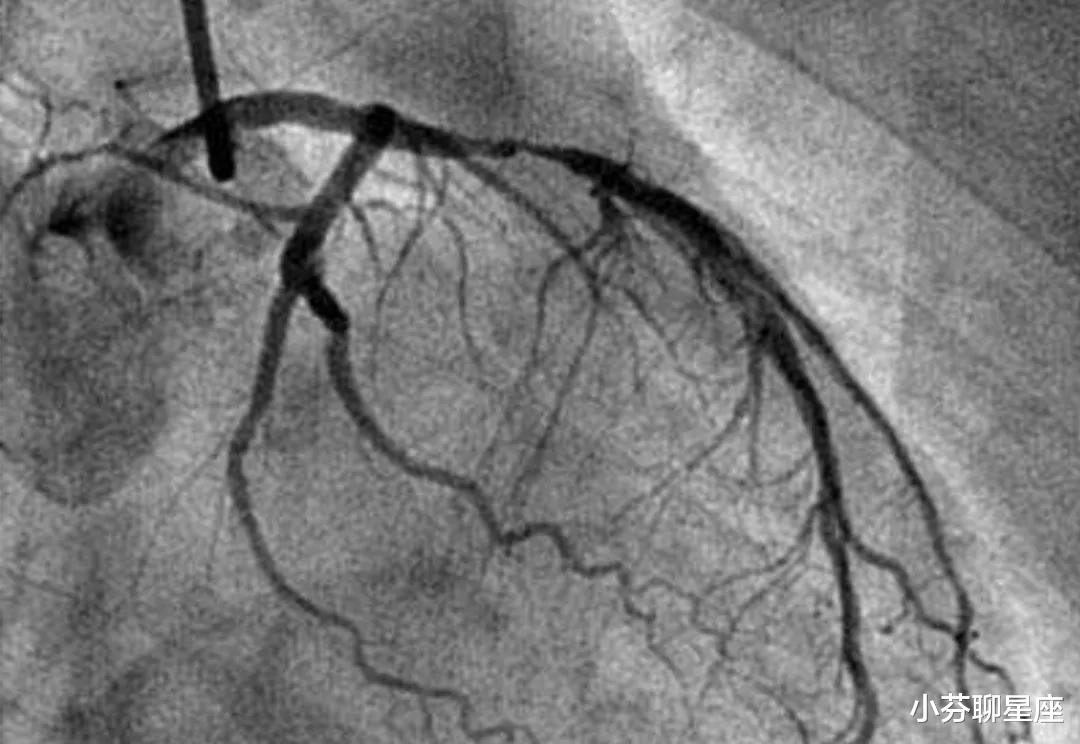

另外 , 很多检查使用的都是一次性耗材 , 而且这些耗材的价格本身就贵 。 就拿冠状动脉造影来说吧 , 这个检查的费用在5000元左右 。 之所以贵 , 一方面是因为它需要用到很多的一次性耗材 , 另一方面这些一次性耗材的价格比一般的一次性耗材高得多 。